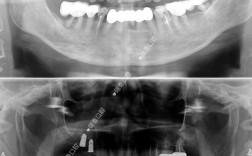

(图片来源网络,侵删)- 挂号: 建议通过南京鼓楼医院的官方渠道(官网、官方APP、微信公众号、电话预约等)提前挂号,选择口腔科或口腔颌面外科,并尽量选择种植牙专科医生或知名专家的号源,知名专家号源可能比较紧张,需提前规划。